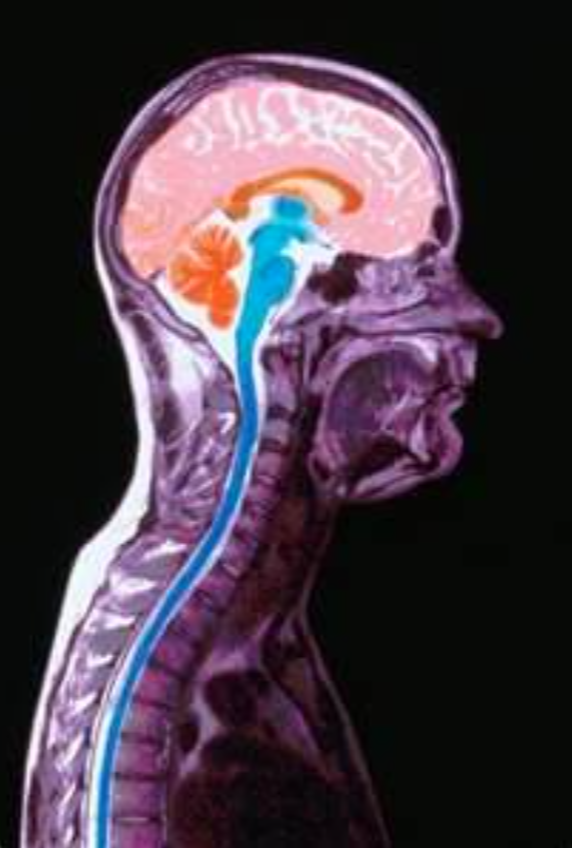

- A Spinal Nerve testing to measure nerve function and;

Chiropractic was founded on its ability to restore nerve function. However, most practitioners lack an effective tool for evaluating their success in correcting patient nerve function.

PRS utilizes one of the most reliable spinal nerve function tests. Recent studies by the American Academy of neurosurgeons have found spinal Thermography to be over 80% accurate for evaluating spinal nerve function.

This tool is one of the foundations in our system of subluxation correction, because it allows you to almost instantly measure the effect of your adjustment on your patient’s nerve function. When used with our pattern analysis software, it is an invaluable tool for clinical use.